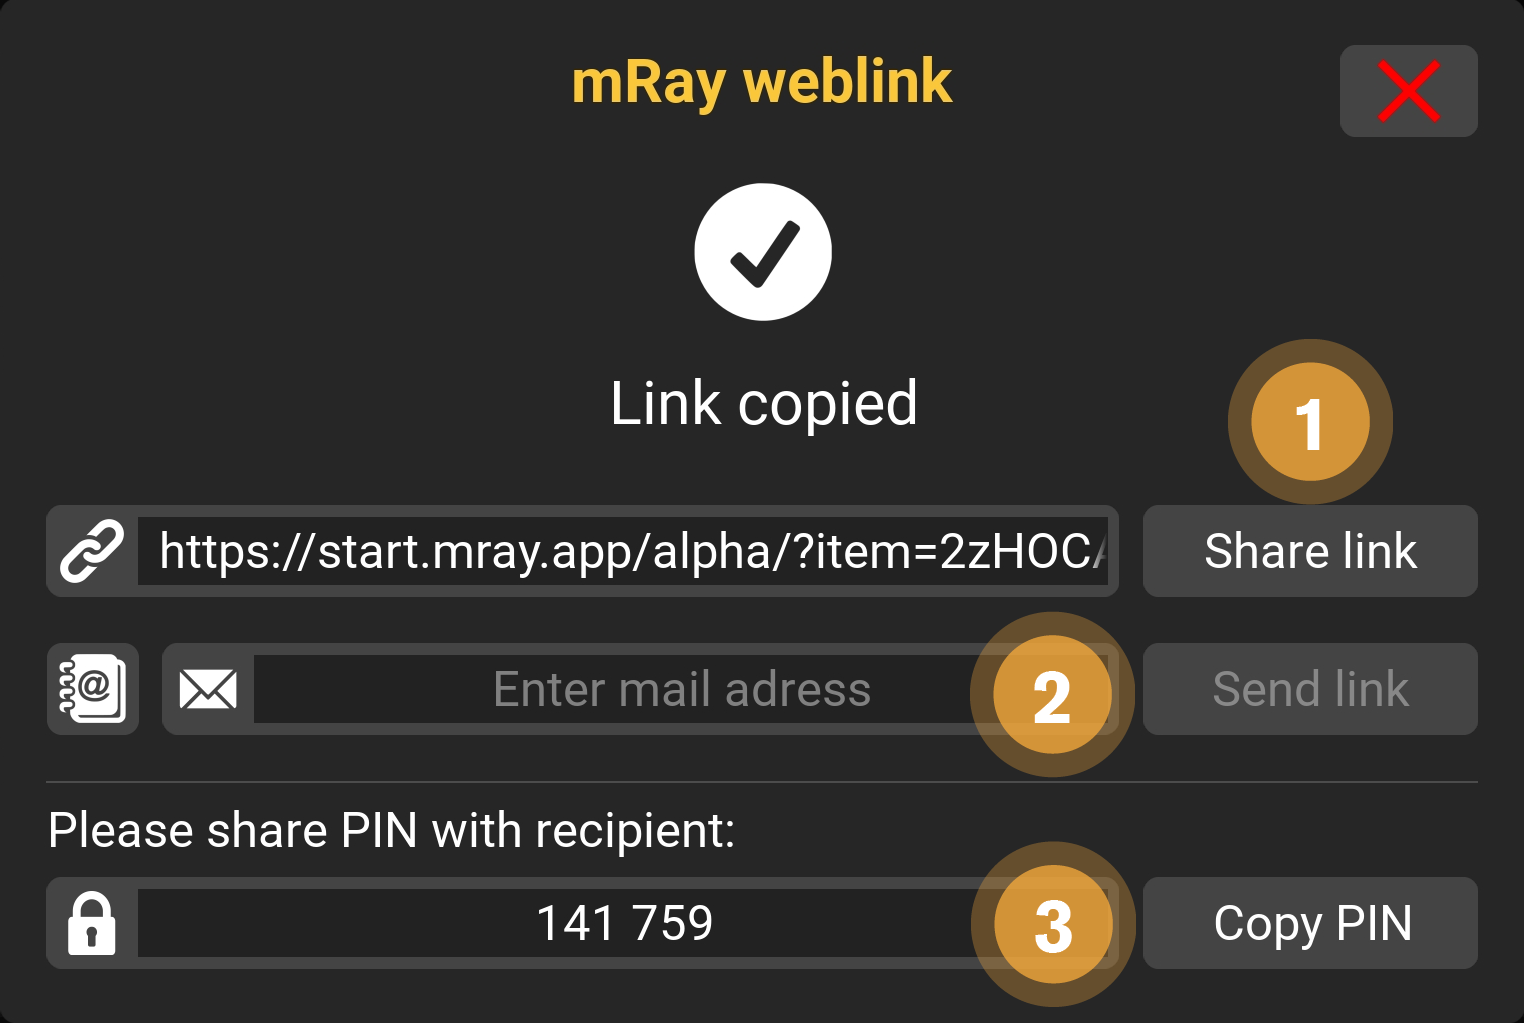

9.14. Link Settings

Various options are available when sharing content via links.

-

You can copy the link manually or tab on "Share link"("copy" on desktop computer) to share with another app.

-

Alternatively you can send the content direct to an Email-address.

-

Send this PIN to your recipient. The content is only visible when entering this PIN